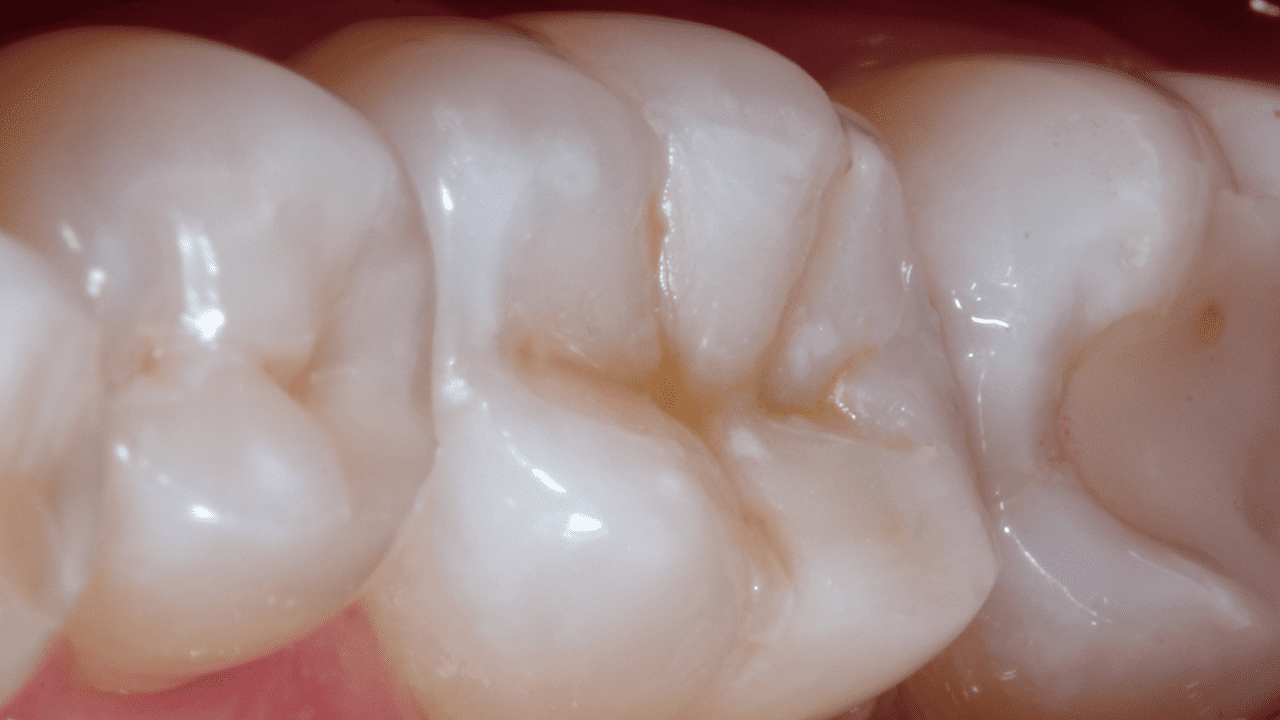

Случай: В случаях, когда гингивальное дно проксимальной полости является поддесневым, процедуру краевого подъема можно выполнить с помощью базового материала SDR plus. После краевого подъема накладывают раббердам и выполняют реставрацию по II классу с использованием соответствующего комплексного решения.

Результаты: По результатам радиографического контроля отмечено превосходное краевое прилегание, плавный переход между композитом объемного внесения SDR plus и композитом Neo Spectra ST, а также отсутствие захвата пузырьков воздуха.